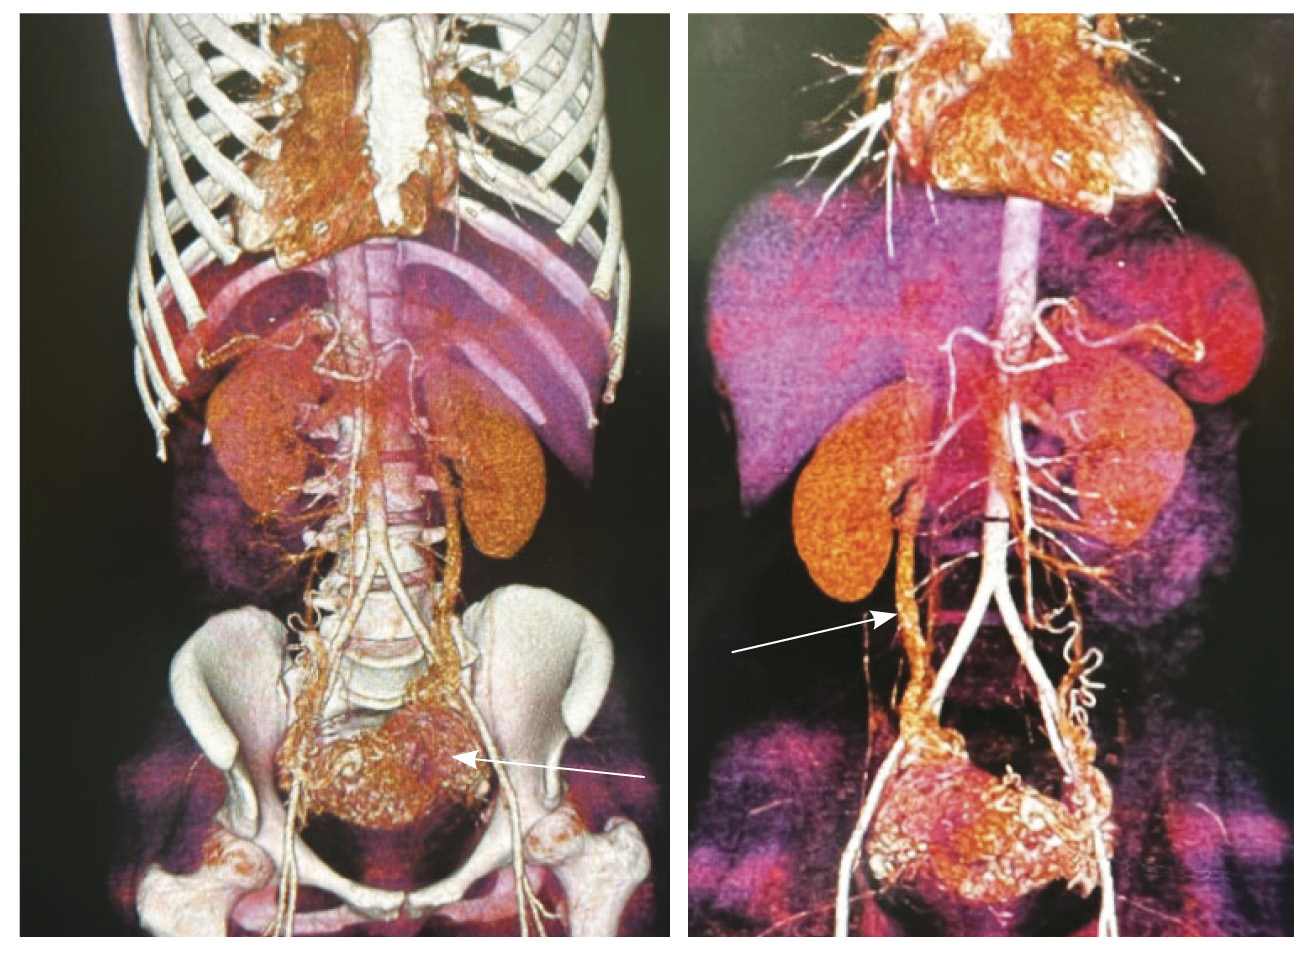

По наружной поверхности нижнего маточного сегмента и в параметрии определяется наличие полнокровной сосудистой сети с артериовенозными анастомозами. При контрастировании визуализируются фрагментарные участки гиперваскулярного накопления контраста вышеописанным образованием в рубцовой нише, а также определяется наличие артериовенозной сосудистой мальформации (рис. 2).

Рис. 2. Магнитно-резонансная томограмма, динамическое контрастное усиление в режиме Т1-взвешенного изображения FS. До контраста (А), в раннюю артериальную фазу (Б), паренхиматозную фазу (В), выделительную фазу (Г) определяются многочисленные патологические сосуды, зоны неоангиогенеза, сосудистые шунты как в стенке матки, так и в параметрии по типу артериовенозной мальформации

Для детализации сосудистого компонента артериовенозной мальформации, в том числе с целью планирования дальнейшей лечебной тактики, пациентке выполнено КТ-исследование (рис. 3). Обнаружено: тело матки увеличено, определяется образование в полости матки неясного генеза. В стенках матки сосудистая артериальная сеть с ранним сбросом контрастного вещества во внутреннюю подвздошную вену с двух сторон (диаметром 0,7 см справа, 0,8 см – слева), правую яичниковую вену (диаметром до 1,2 см), левую яичниковую вену (диаметром до 0,6 см).

Рис. 3. Компьютерная томограмма органов таза с контрастированием. Тело матки увеличено, в стенках матки сосудистая артериальная сеть (стрелки) с ранним сбросом контрастного вещества во внутреннюю подвздошную вену с двух сторон, правую и левую яичниковые вены (стрелка)